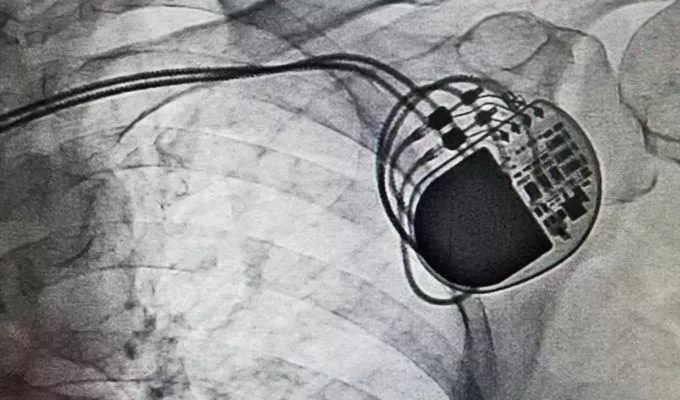

据外媒securityaffairs报道,2017年5月美国食品和药物管理局(FDA)正在召回大约50万个起搏器,因为它们很容易受到黑客的攻击。黑客利用漏洞重新编程,可以停止心脏起搏器电池的运作或者修改心脏跳动的方案,在发现这个漏洞后,FDA已召回465000心脏起搏器。

跟全球肆虐的勒索病毒比起来,前者也就是让你破点财,后者则是要你命!两起事件都是运用攻击性手段利用漏洞对网络安全形成威胁,从而达到索取金钱的目的。面对如此来势汹汹的劲敌,从哪些方面着手才可以让黑客无处可寻呢?其实,安全漏洞问题的关键在于“预防“,通过规范网络行为,加强网络监控,做好漏洞预防是应对安全漏洞的主要手段之一。